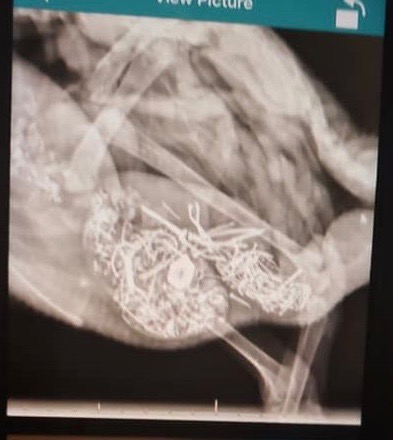

Pica

Bitchin’ Chickens: In people, pica is used to describe compulsive eating of non-food items, such as ashes, clay, and flaking paint. It’s mostly seen in young children or adults with intellectual and developmental disabilities. Pica involving eating dirt may be related to an iron or zinc deficiency. Poultry that eat foreign objects can suffer impaction, perforation of the digestive tract or metal toxicity.

Dr Bowes: This is a case of pica which has several implications: punctures from the sharp nails and screws, and zinc or lead poisoning from the metals. It’s great that the owner had an x-ray done to determine what was going on, but this issue won’t be remedied without surgical intervention. I would be curious what the environment was like that the duck had access to that many metal objects, why it was attracted to eating them and what were its symptoms that required a visit to the vet?